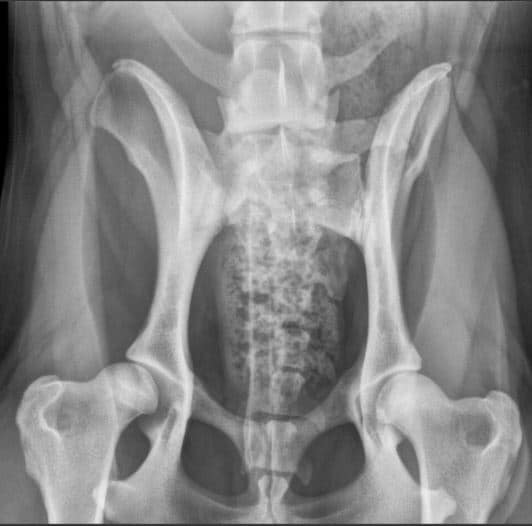

A normal canine spine consists of 7 cervical (C1-7), 13 thoracic (T1-13), 7 lumbar (L1-7) and 3 sacral vertebras (S1-3) resulting the total of 30 vertebras. Calculation starts from first thoracic vertebra (T1). The number of caudal vertebras (CD) vary.

Sacrum connects the lumbar spine to pelvis. It’s a part of the pelvis and it lies between the lumbar spine and tail. Sacrum is strong, triangular in shape and it sits between the hip bones. Normal sacrum consists of three fused vertebral segments; S1, S2 and S3.